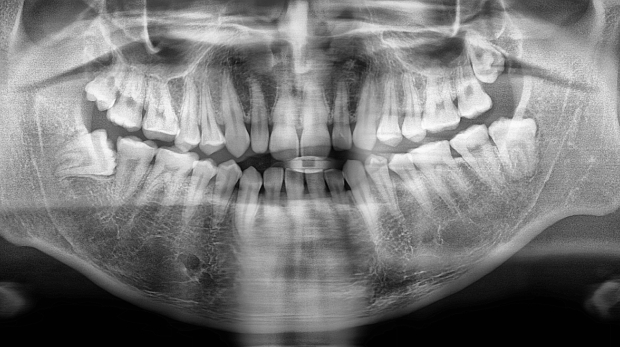

박** 환자분 (오른쪽 상하악 사랑니 동시 발치 케이스)

상악의 경우 단순매복으로 발치 및 동시에 하악 잇몸뼈에

깊게 박혀잇는 고난이도 케이스, 잇몸절개 후 치아 분리하여

발치하였으며

해당환자 치과공포증이 있으셨으나 본원 수면치료 병행하여 편안한

수술 진행되어 만족하심